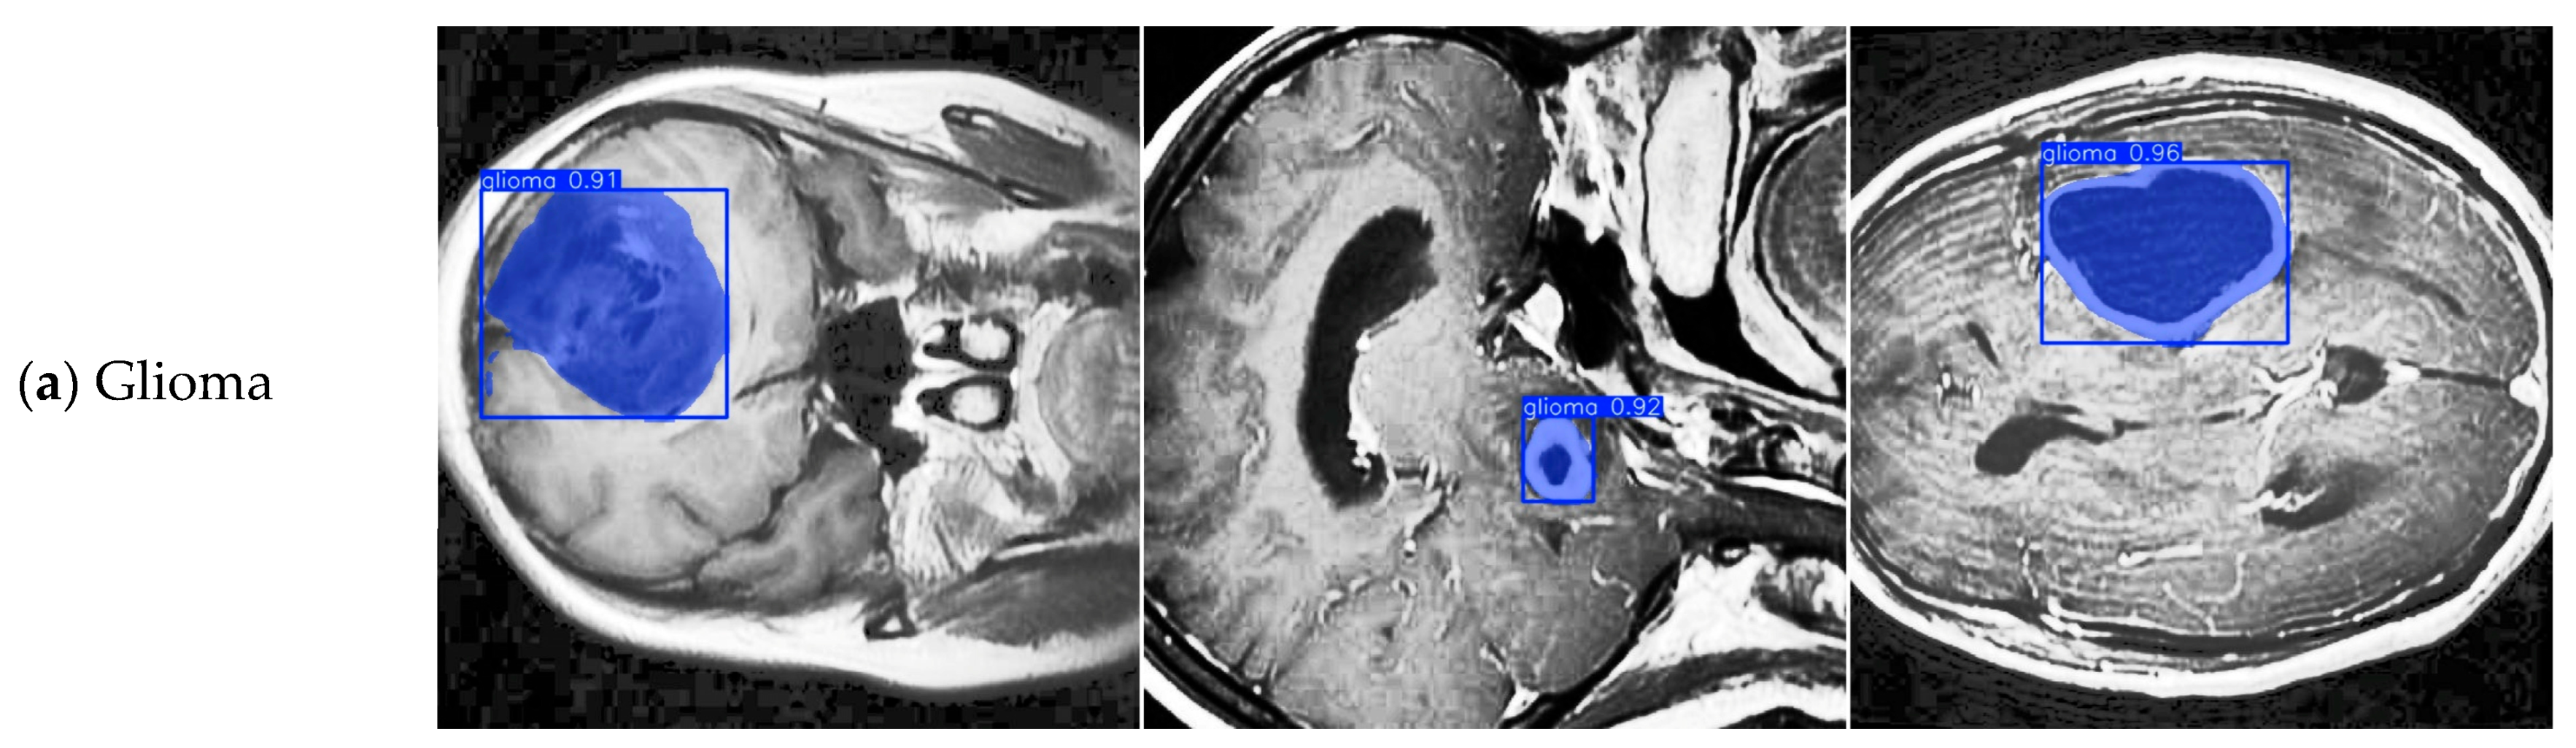

4.4. Model Training, Testing, and Results Analysis

| Class | FALS-YOLO Correct Classification | FALS-YOLO Misclassification | YOLOv8-Seg Correct Classification | YOLOv8-Seg Misclassification |

|---|---|---|---|---|

| Glioma | 132 | 40 | 124 | 37 |

| Meningioma | 58 | 10 | 56 | 6 |

| Pituitary | 81 | 10 | 78 | 5 |

| Background | - | 31 | - | 42 |